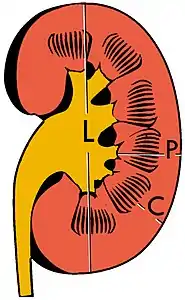

The kidney is divided into parenchyma and renal sinus. The renal sinus is hyperechoic and is composed of calyces, the renal pelvis, fat and the major intrarenal vessels. In the normal kidney, the urinary collecting system in the renal sinus is not visible, but it creates a heteroechoic appearance with the interposed fat and vessels. The parenchyma is more hypoechoic and homogenous and is divided into the outermost cortex and the innermost and slightly less echogenic medullary pyramids. Between the pyramids are the cortical infoldings, called columns of Bertin (Figure 1). In the pediatric patient, it is easier to differentiate the hypoechoic medullar pyramids from the more echogenic peripheral zone of the cortex in the parenchyma rim, as well as the columns of Bertin (Figure 2).[1]